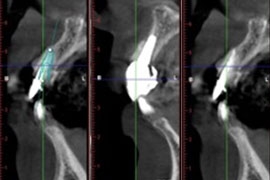

3D電腦斷層微創植牙

立即植牙及3D立體斷層掃描

3D電腦斷層 微創植牙